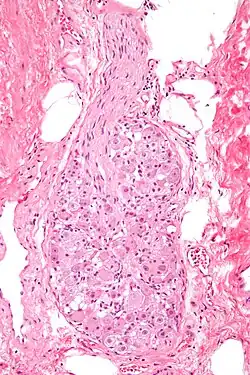

Histologisches Bild eines Ganglions

Sensible Ganglien enthalten die Nervenzellkörper (Soma) sensibler Neurone. Sensible Ganglien besitzen alle Rückenmarksnerven in Form der Spinalganglien. Sie enthalten pseudounipolare Nervenzellen und sind von einer Bindegewebskapsel umgeben, von der Trabekel in das Innere ziehen und im Inneren ein Stützgerüst, das Stroma, bilden. Auch die Hirnnerven III und VII bis X besitzen solche Ganglien, der VIII. Hirnnerv besitzt aber, im Gegensatz zu den übrigen, bipolare Ganglienzellen. Die Nervenzellen sensibler Ganglion nehmen über ihren Dendrit Informationen aus der Umgebung auf und leiten sie über ihr Axon an das Zentralnervensystem weiter.[1]

Autonome (Vegetative) Ganglien sind im Autonomen Nervensystem zu finden. Sie besitzen ebenfalls eine Bindegewebskapsel, mit Ausnahme der Ganglien in der Wand des Darms (intramurale Ganglien). Autonome Ganglien enthalten multipolare Nervenzellen. Im Gegensatz zu den sensiblen Ganglien erfolgt in den autonomen Ganglien eine Umschaltung auf eine zweite (postganglionäre) Nervenzelle über Synapsen. In diesen Ganglien werden also Informationen von einer auf eine andere Nervenzelle weitergeleitet.[1]